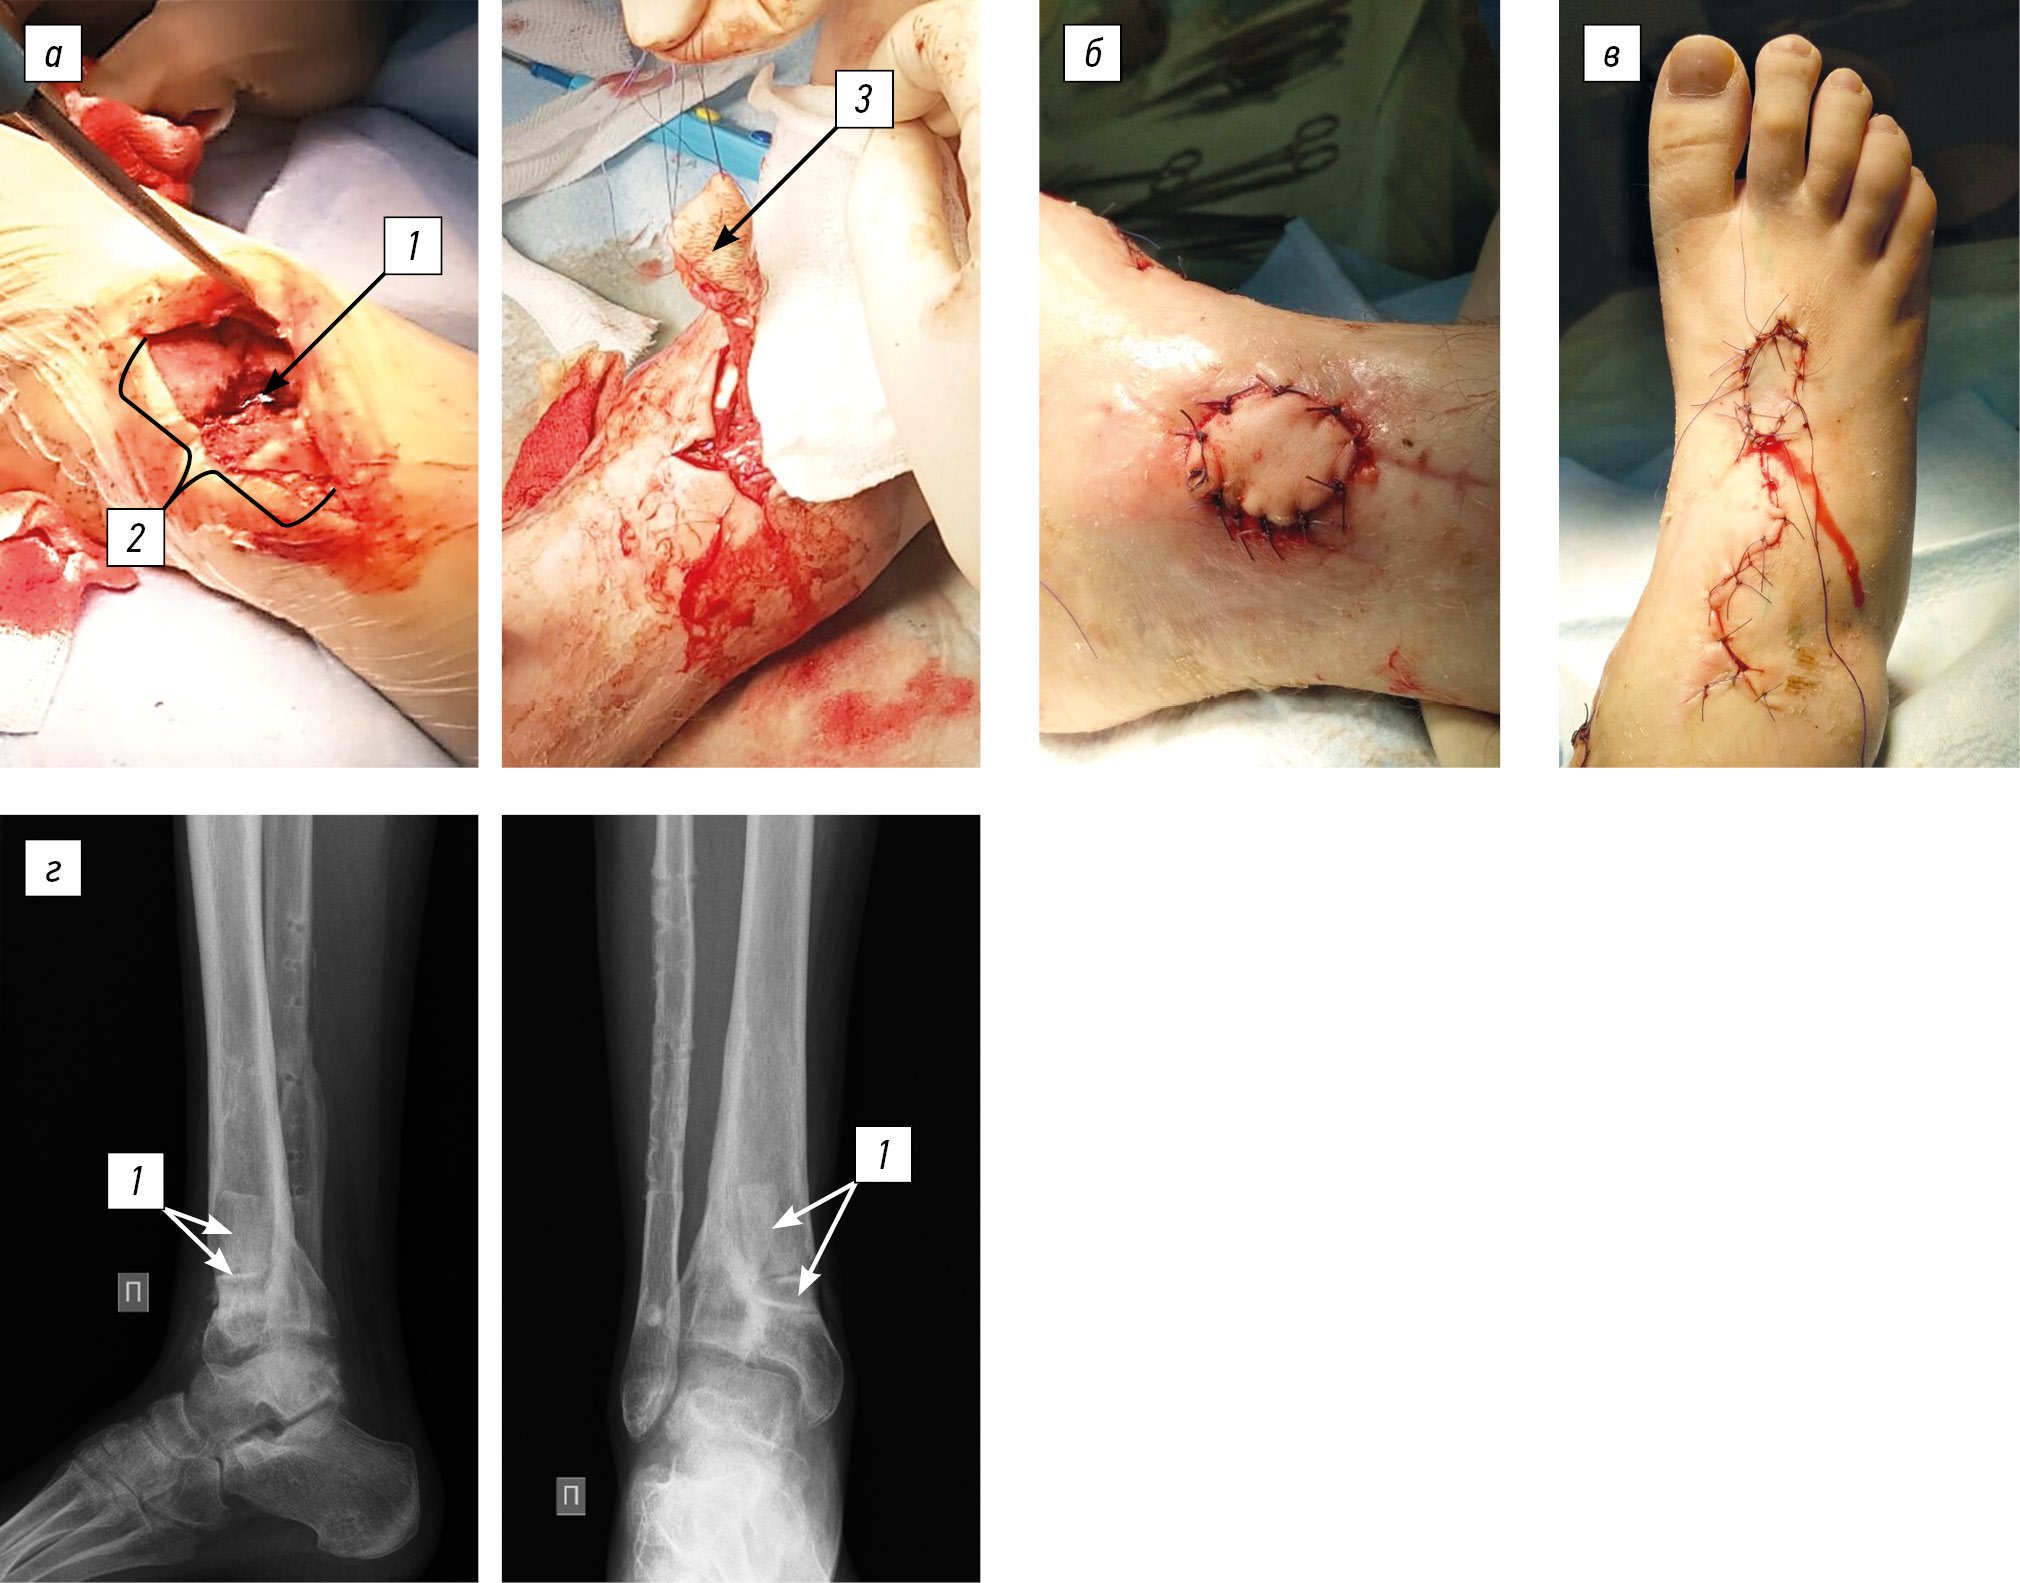

Considering the course of chronic osteomyelitis, complicated by a fistulous process with trophic changes in soft tissues, radical reconstructive intervention was decided, which included the removal of the hardware of the right fibula, fistulectomy of the lower third of the right tibia, osteonecrectomy of the distal metaphysis of the right tibia, bone autografting of the defect (iliac crest), plastic surgery of a wound defect using an islet dorsal foot graft with axial blood flow, and plastic surgery of the donor wound with a split skin graft (Fig. 5). Histological examination revealed chronic nonspecific inflammation with exacerbation, and bacteriological examination revealed S. aureus 103 with high sensitivity. The patient received a course of antibacterial therapy with cefazolin at an age-appropriate dose. In dynamics, the infectious and inflammatory process stopped. Control radiographs after 6 months showed the integration of bone grafts (Fig. 6). The support ability of the limb has been restored; when walking >1.5 km, she experienced pain (up to 3 points on the visual analog scale) in the ankle joint. The shortening did not increase during the follow-up period.

Fig. 5. Surgical wound (a): 1, zone of destruction; 2, wound defect after excision of the fistula; 3, dorsal foot flap on a vascular pedicle. The wound defect after fistulectomy is closed with a vascularized graft (b), a donor wound (c), control radiograph of the ankle joint in two views, and bone autoplasty of the tibial defect is determined (d): 1, bone grafts